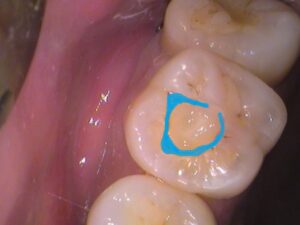

青く示している所です。

歯の詰め物は全て、歯と接着していなければ意味がありません。

・歯と詰め物との接着が剥がれてしまっている場合。

・詰め物が歯と合っていない(ズレている)、ちゃんとフィットしていない場合。

など、歯に隙間があれば細菌が侵入していきます。

細菌の大きさ、サイズは1μmと、

1mmの1000分の1の大きさです。

目に見えない細菌は、目に見えない隙間でも入り込みます。

ましてや目に見える隙間は容易にどんどん侵入していきます。

今回の様に、歯と詰め物に大きな隙間がある場合、

内部で虫歯になっている可能性も高くなります。